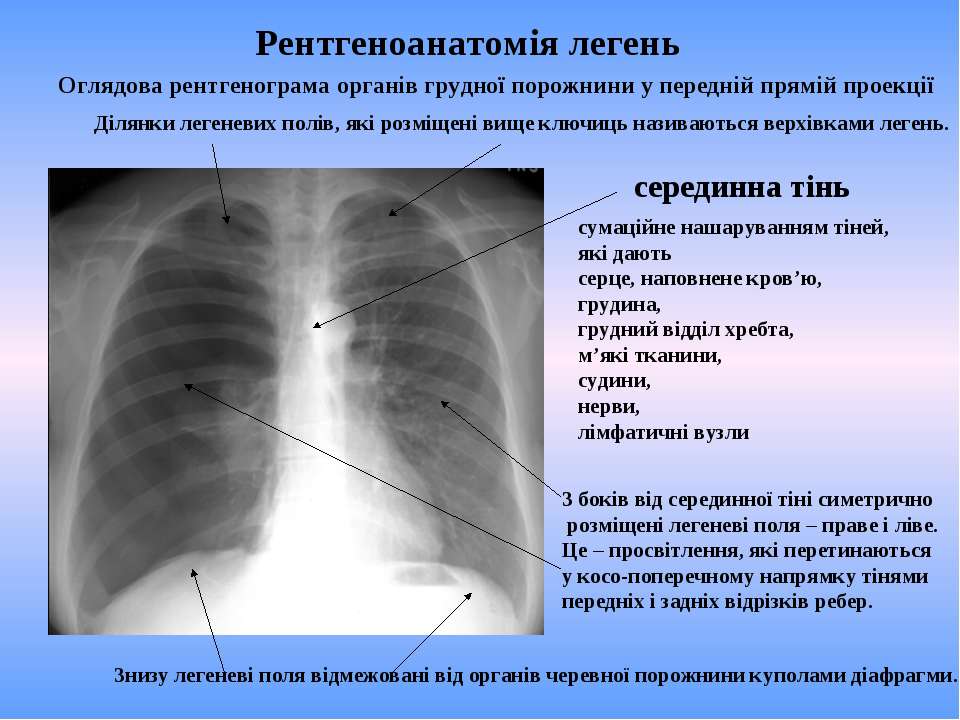

Нормальная рентгенограмма легких: что нужно знать

Раздел: Мудрость в объективе